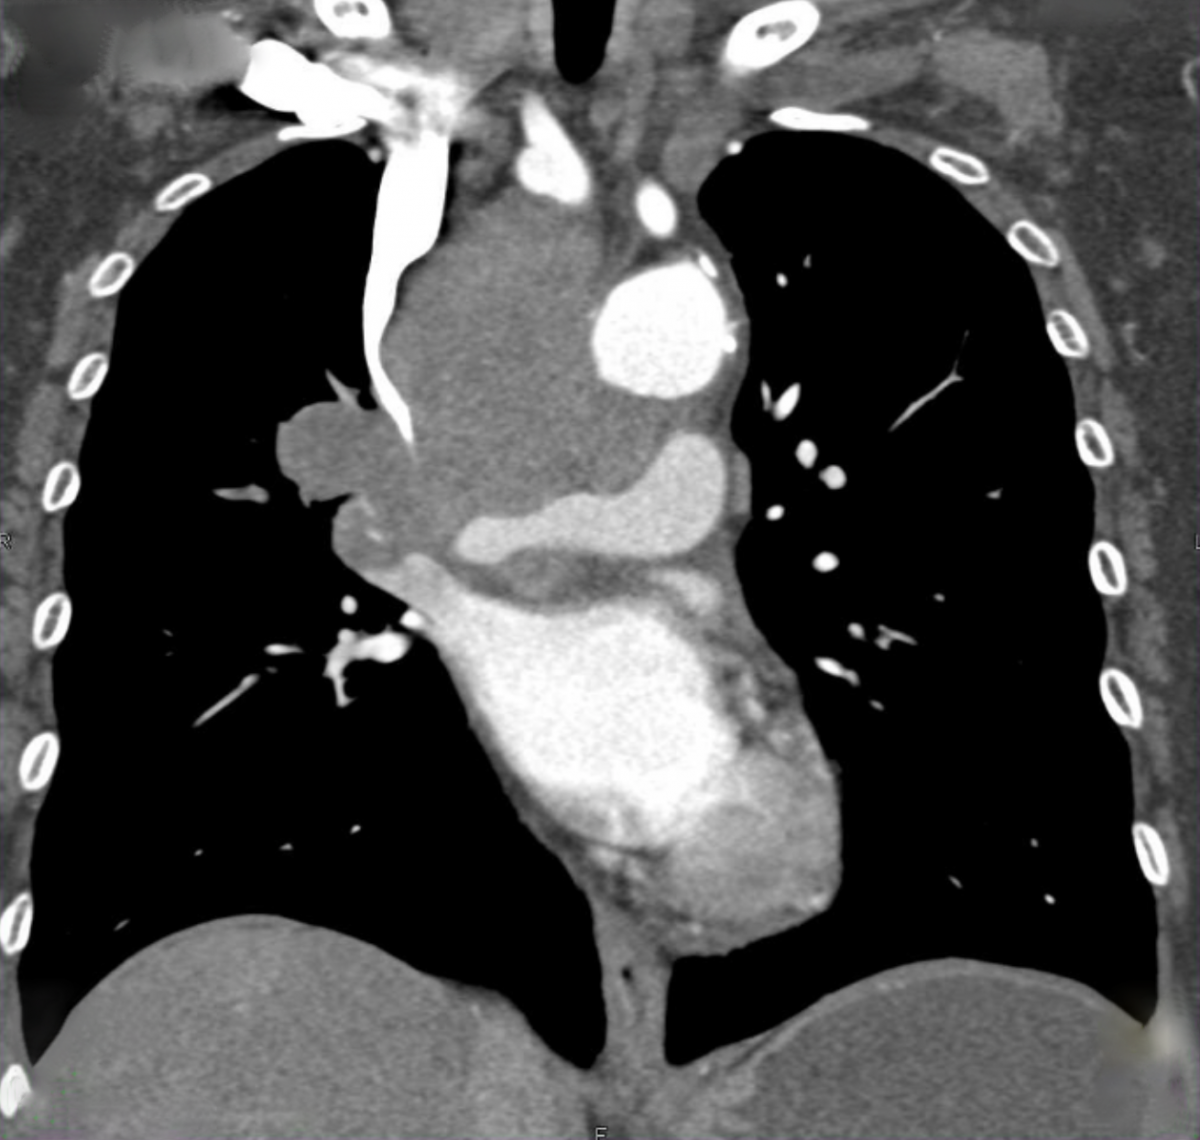

Patient presents with neck and facial swelling and is complaining of shortness of breath. CXR is here, what's the diagnosis? (scroll down for answer)

Answer: SVC Syndrome

SVC Syndrome

- Most commonly caused by an obstructing malignancy (i.e. lung cancer)

- Thrombosis is another common cause due to central venous catheters or pacemakers

- The severity of symptoms will depend on the location and speed of obstruction especially if venous collaterals do not have time to develop (typically at the azygos or post-azygos vein, pre-azygos typically presents more insidiously)

- Symptoms include facial plethora, flushed face, distended neck veins, dyspnea, cough, hoarseness

- If respiratory compromise is imminent due to extrinsic compression, patients may benefit from emergent stent placement and radiotherapy; thrombolysis and anticoagulation may be necessary if the cause is a thrombus